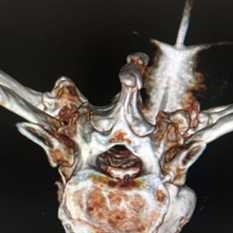

(Слева) Рентгенография черепа в боковой проекции: определяется хорошо заметное расширение диплоического пространства, преимущественно сзади. При талассемии преимущественное поражение затылочной кости встречается нечасто, но именно это наблюдается в данном случае. Околоносовые пазухи в этом возрасте должны быть заполнены воздухом, но здесь они почти полностью замещены костным мозгом.

(Справа) Бесконтрастная КТ, аксиальный срез: у пациента с большой талассемией определяются расширение и облитерация околоносовых пазух, обусловленные гиперплазией костного мозга. (Слева) Бесконтрастная КТ, аксиальный срез: у этого же пациента определяется гиперплазия верхнечелюстных пазух. Воздуха в них нет. Расширение околоносовых пазух при этом заболевании приводит к искажению черт лица, характерному для талассемии и называемому «мышиным лицом».

(Слева) Рисунок: талассемия черепа. Показано выраженное истончение кортикальных пластинок, расширение диплоического пространства и открытая порозная губчатая кость. Коричневато-красный цвет обусловлен распространенным отложением железа в коаном мозге.

(Справа) Бесконтрастная КТ, аксиальный срез: определяется выраженное утолщение диплоического костномозгового пространства. Щажение затылочной кости относительно передних областей встречается часто. (Слева) Бесконтрааная КТ, аксиальный срез: у этою же пациента определяется выраженное расширение диплоического пространства с поражением как лобных, так и теменных отделов черепа. Кортикальные пластинки обоих слоев черепа истончены до той степени, что не определяются.

(Справа) Рентгенография черепа в боковой проекции, изображение урезано: у пациента с большой талассемией определяется выраженное расширение диплоического пространства с характерной картиной губчатой кости, расположенной между значительно истонченными наружной и внутренней кортикальным пластинками костей черепа, по типу «волос дыбом».